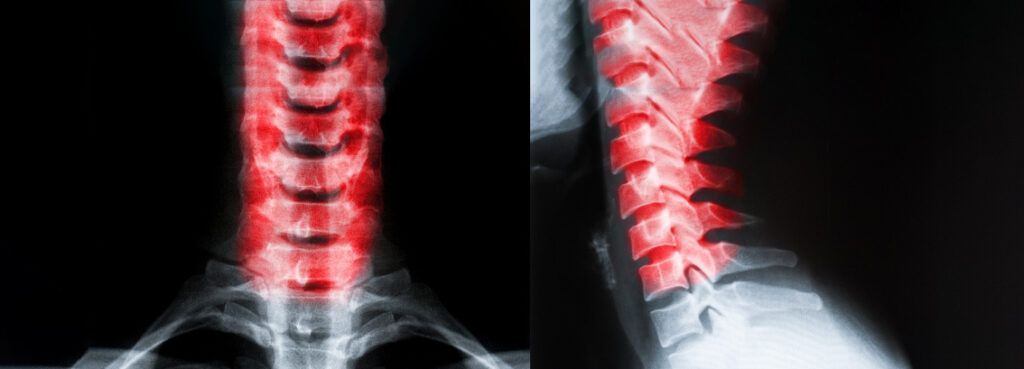

Neck Pain

Treatment options include nerve alignment using a gentle pressure. It may also include massage so that muscles relax and allow the bones to go back into alignment.